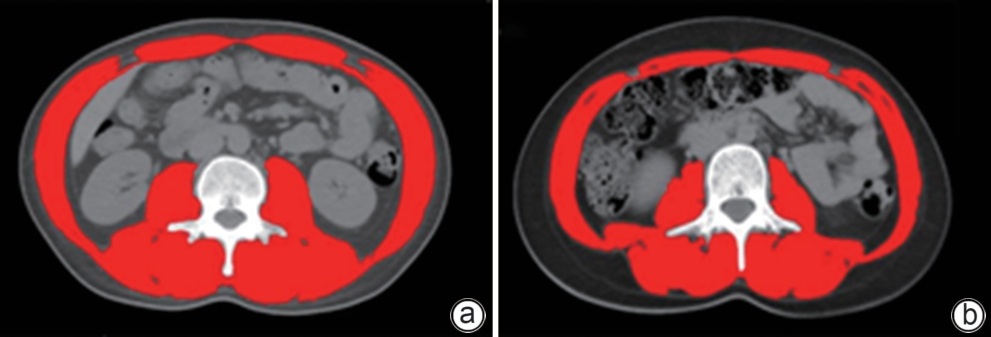

Wilson病肝硬化并发肌肉减少症的危险因素及其对临床结局的影响

王玮琦, 魏涛华, 钱南南, 杨文明, 杨玉龙, 宋宇琪, 郝文杰, 杨悦, 席虎, 何伟

2025, 41(10): 2075-2081. DOI: 10.12449/JCH251018

摘要:

目的  研究Wilson病肝硬化患者中肌肉减少症的发生情况,探讨肌肉减少症发生的危险因素及其对临床结局的影响。  方法  纳入2019年1月—2020年6月在安徽中医药大学第一附属医院接受治疗的140例Wilson病肝硬化患者,根据第三腰椎骨骼肌质量指数(L3 SMI)将患者分为肌肉减少症组和无肌肉减少症组。对纳入患者进行营养风险筛查、人体测量、血生化指标检测,比较两组相关指标的差异,筛选并发肌肉减少症的影响因素。随访36~48个月,比较两组患者生存状况、并发症发生情况。符合正态分布的计量资料2组间比较采用成组t检验;计数资料2组间比较采用χ2检验或Mann-Whitney U秩和检验。采用二元Logistic回归分析肌肉减少症的影响因素;通过单因素及多因素Cox回归分析影响Wilson病肝硬化患者预后的危险因素,绘制Kaplan-Meier生存曲线,采用Log-rank检验比较组间生存情况。  结果  Wilson病肝硬化中并发肌肉减少症患者53例(37.9%),其身体质量指数(BMI)和L3 SMI明显低于无肌肉减少症患者(t值分别为10.550、3.982,P值均<0.001)。Logistic多因素回归分析结果显示,Wilson病肝硬化患者并发肌肉减少症的主要影响因素为年龄(OR=2.243,95%CI:1.196~4.208,P=0.012)、性别(OR=0.450,95%CI:0.232~0.872,P=0.018)、BMI(OR=0.126,95%CI:0.089~0.294,P<0.001)、肝性脑病(OR=8.367,95%CI:2.423~28.897,P<0.001)。并发肌肉减少症患者的病死率(χ2=6.158,P=0.019)以及感染(χ2=8.008,P=0.040)、反复腹/胸腔积液(χ2=17.742,P<0.001)、肝性脑病(χ2=4.338,P=0.039)的发生率均高于无肌肉减少症者,差异均有统计学意义。多因素Cox回归分析显示,肌肉减少症(HR=4.685,P=0.002)和肝性脑病(HR=19.156,P<0.001)为影响Wilson病肝硬化患者死亡的独立危险因素。Kaplan-Meier生存曲线提示,并发肌肉减少症的患者生存率显著下降(P=0.003)。  结论  肌肉减少症是Wilson病肝硬化患者营养不良的表现之一,其病死率、其他并发症的发生风险升高,对预后产生不良影响。男性患者、并发肝性脑病、BMI水平越低、年龄越大,肌肉减少症的发生风险越高。